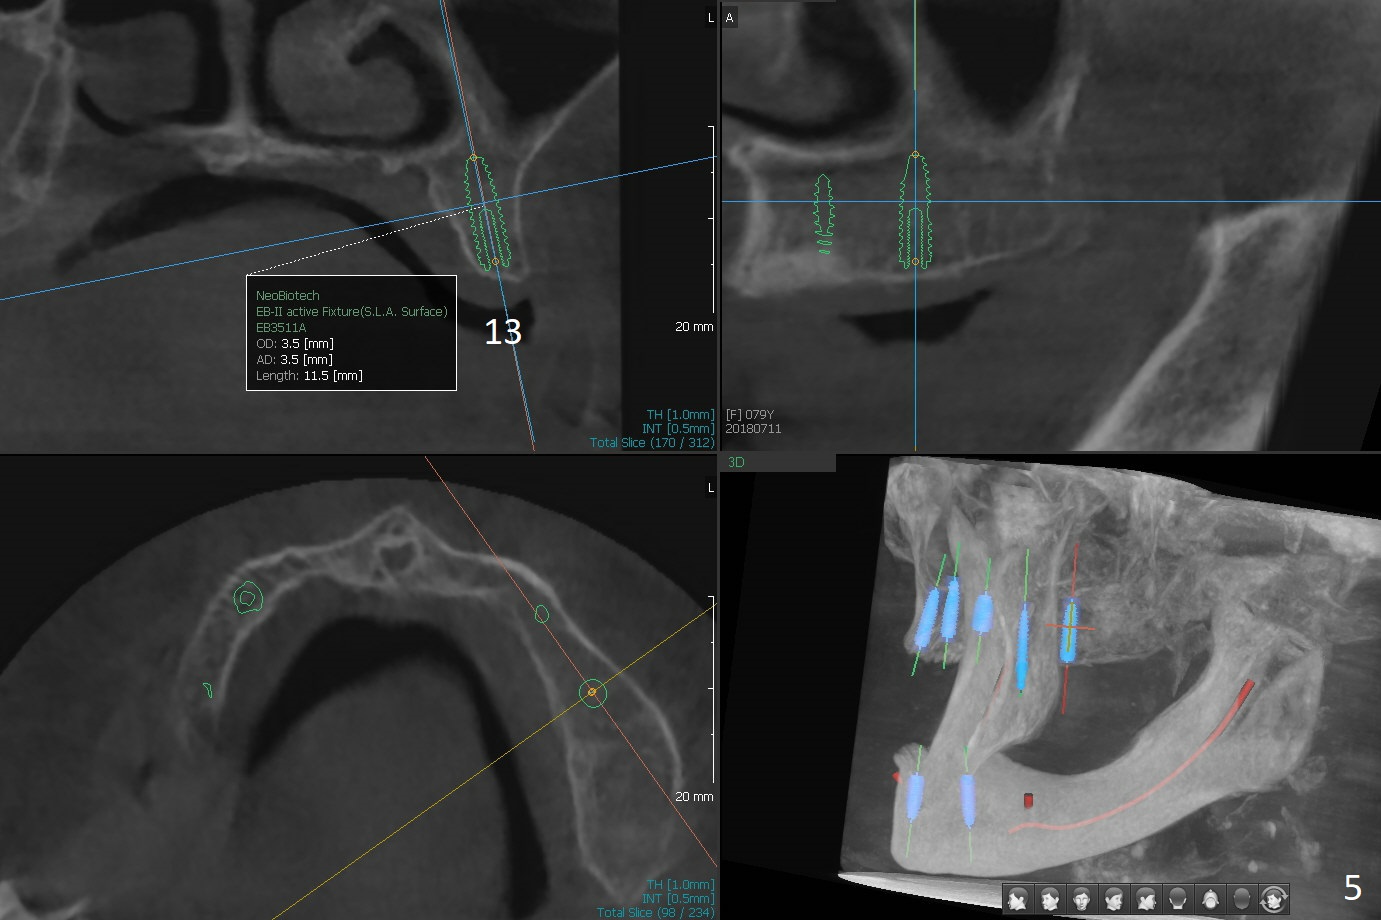

A 80-year-old woman wants to correct cross bite of complete dentures (Class II relationship). It seems that implant supported overdentures can make it possible (retention). Six implants will be placed in the maxillary canine and 2nd premolar and 2nd molar areas with surgical guide (Fig.1-6 (anterior ridge narrow)). Bone density is low. Prepare soft reline.